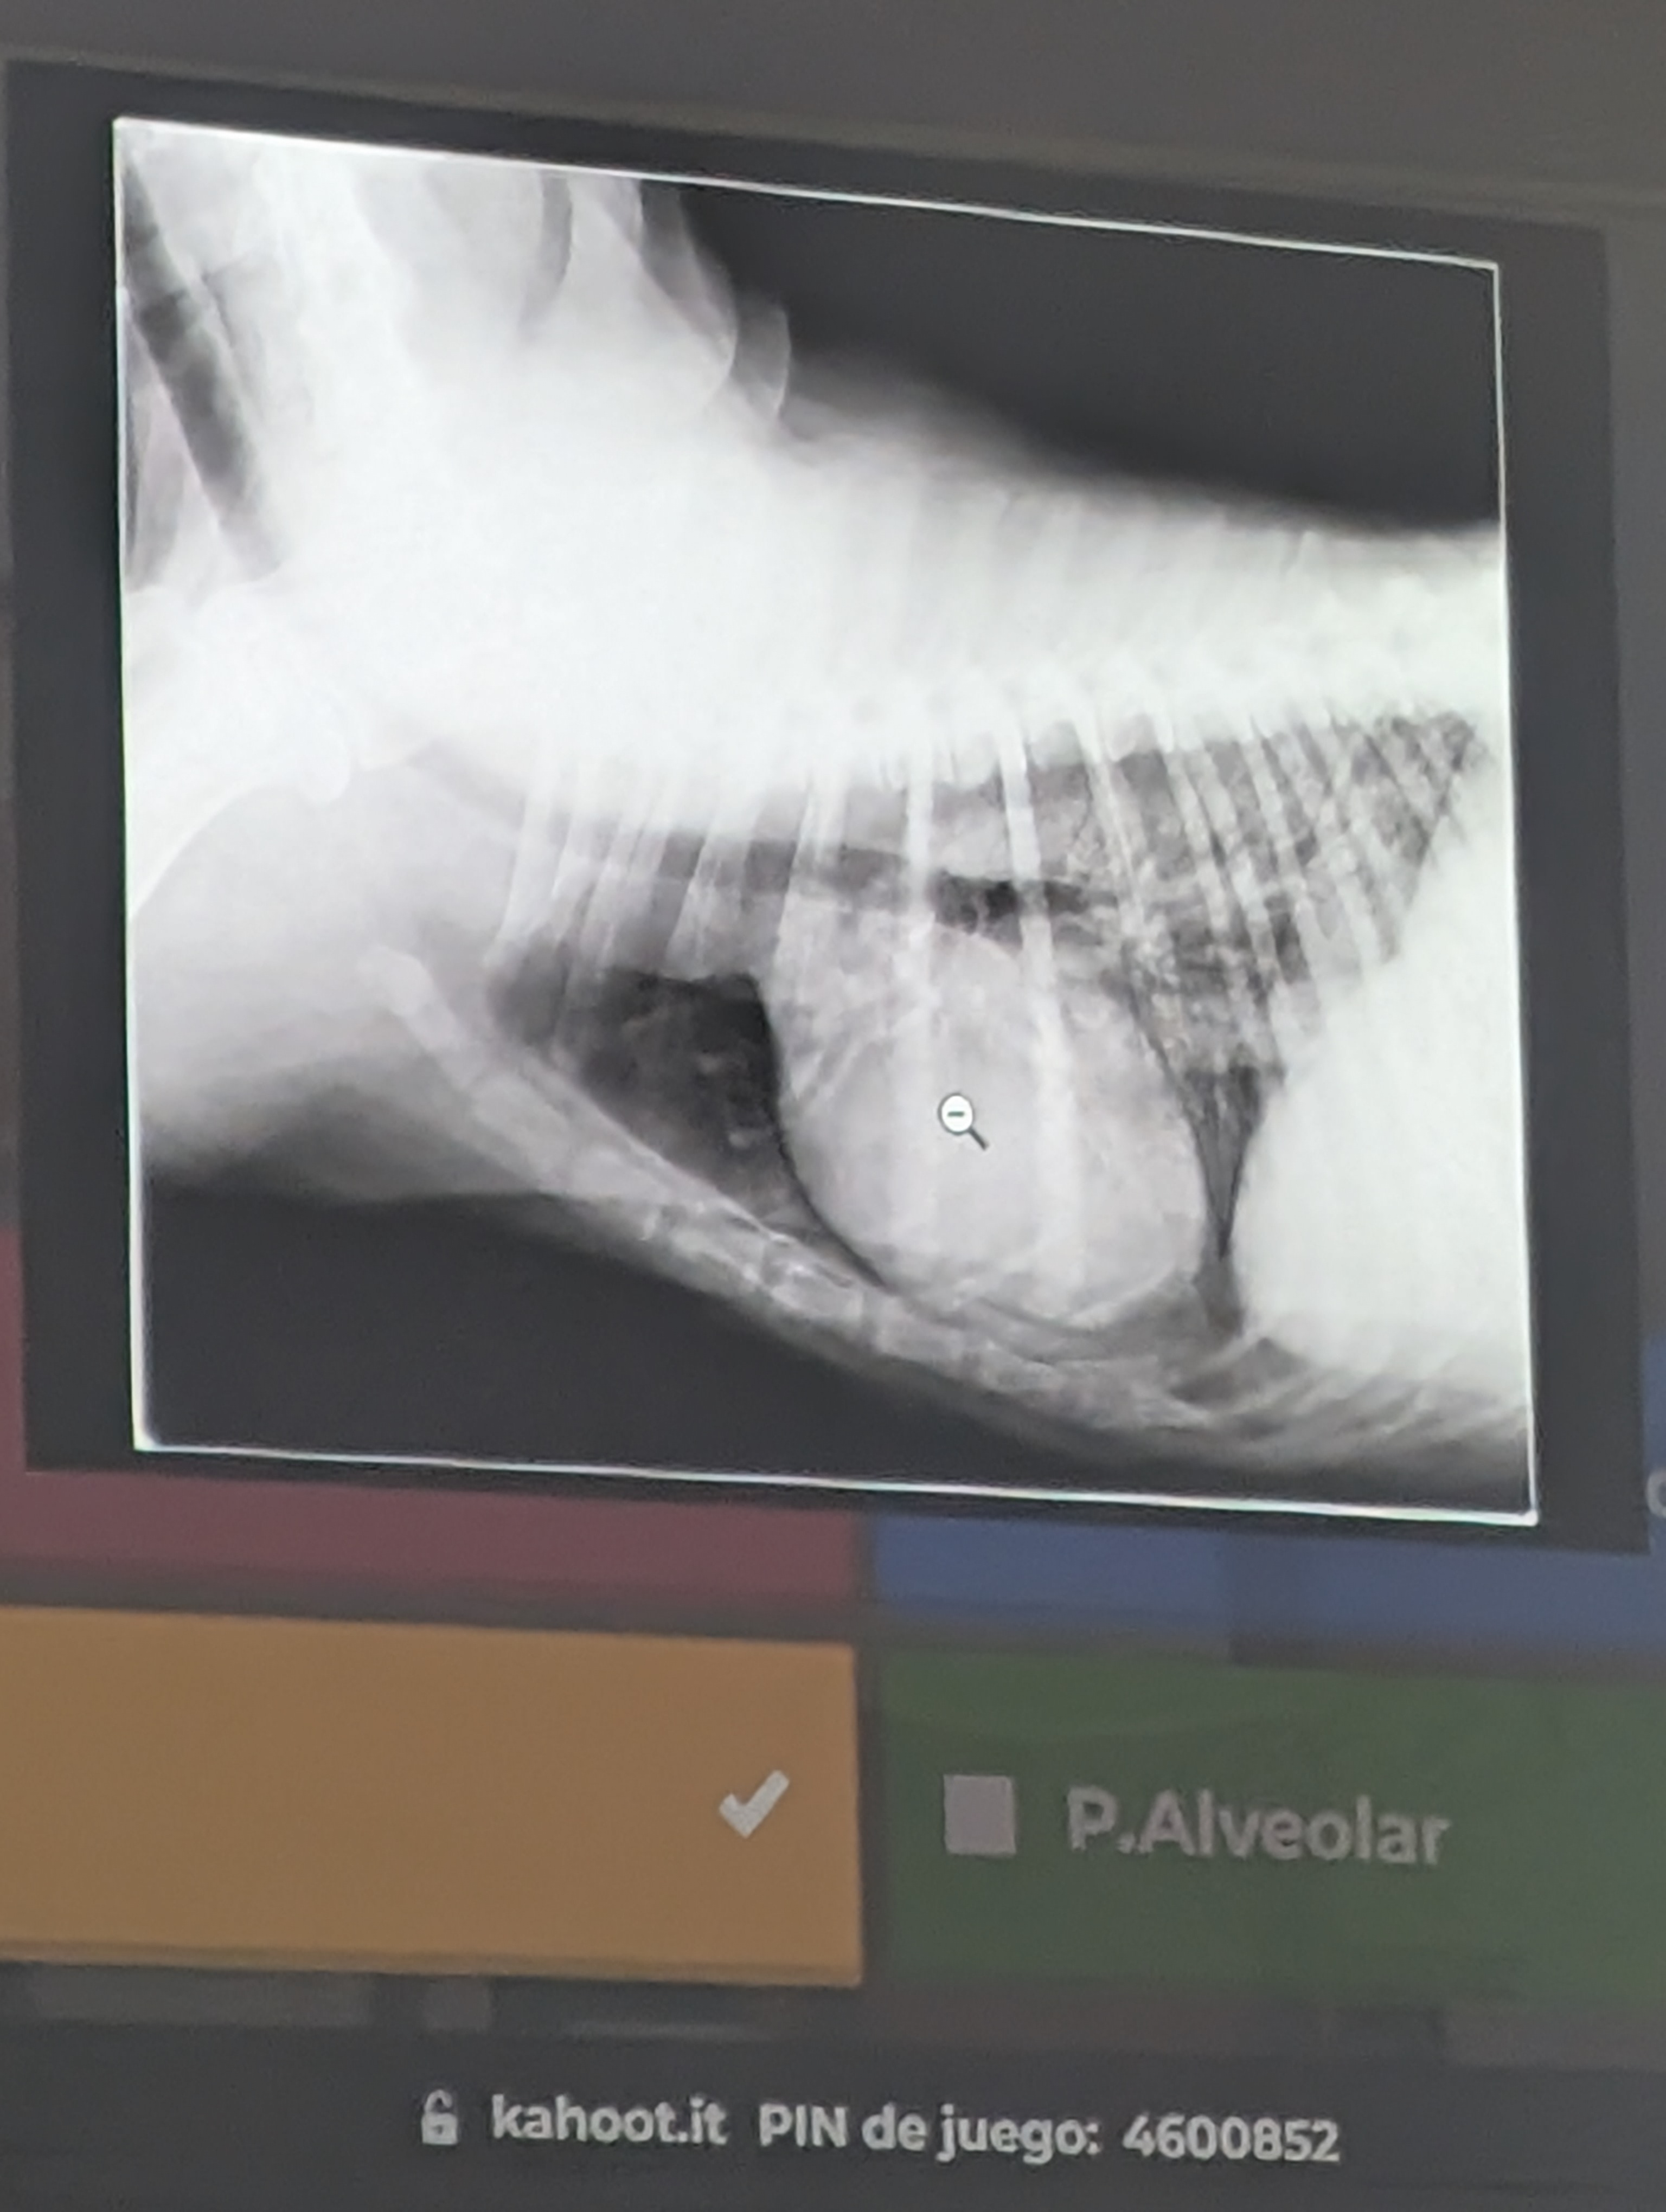

Preguna 1 - Multiple respuesta

- Se trata de un abdomen de gato

- Obstrucción intestinal

- Presenta una dilatación gastrica sin torsión (ya que el fundus y piloro gastrico están en su sitio).